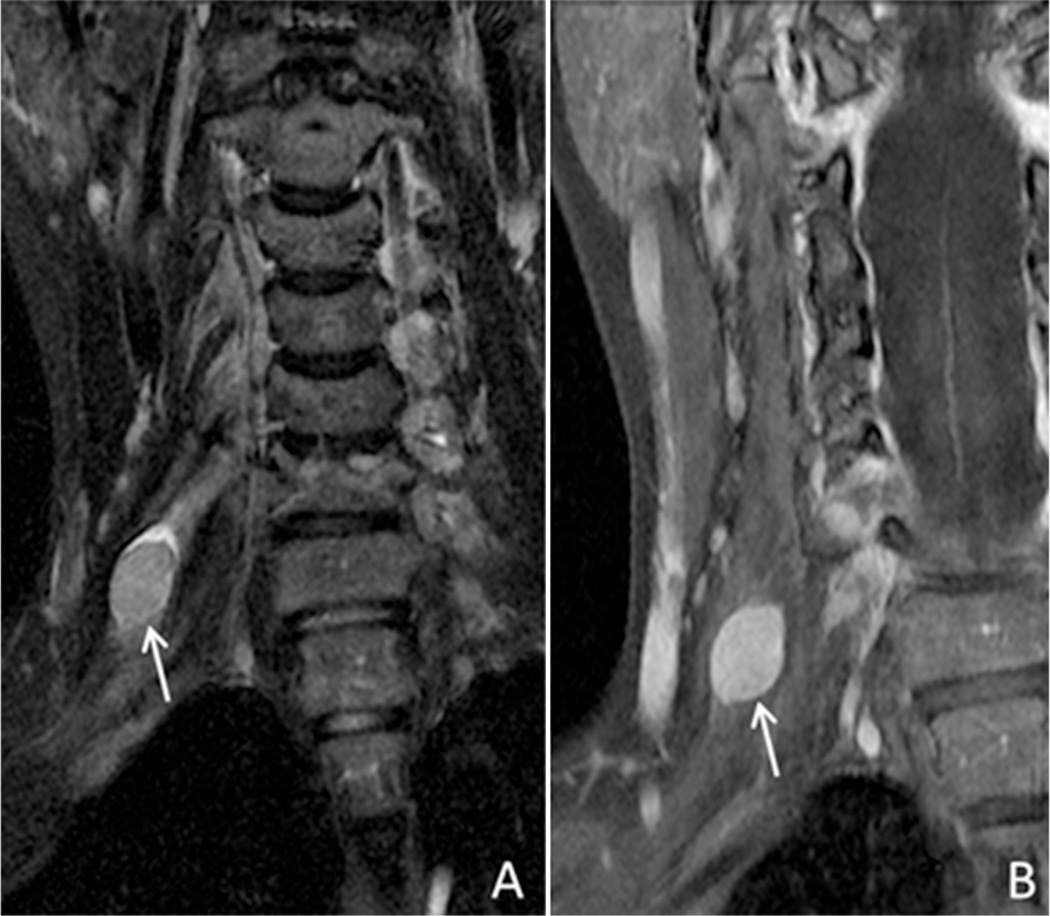

Schwannomas have a true capsule composed of epineurium and are easily separated from the associated nerve at surgery. Schwannomas often demonstrate a higher rate of cystic degeneration and/or hemorrhage than other nerve sheath tumors. Fig. 7 demonstrates images obtained in a patient with persistent right radicular symptoms. Dedicated imaging of the brachial plexus demonstrated a mass associated with the C5 nerve root, which was pathologically proven to be schwannoma.

Fig. 7.

36 year old female with schwannoma. Coronal T2 IDEAL (A) and coronal T1 IDEAL following contrast administration (B) demonstrate a T2 heterogeneous, homogeneously enhancing well circumscribed mass associated with the C5 nerve root, consistent with schwannoma (arrows).